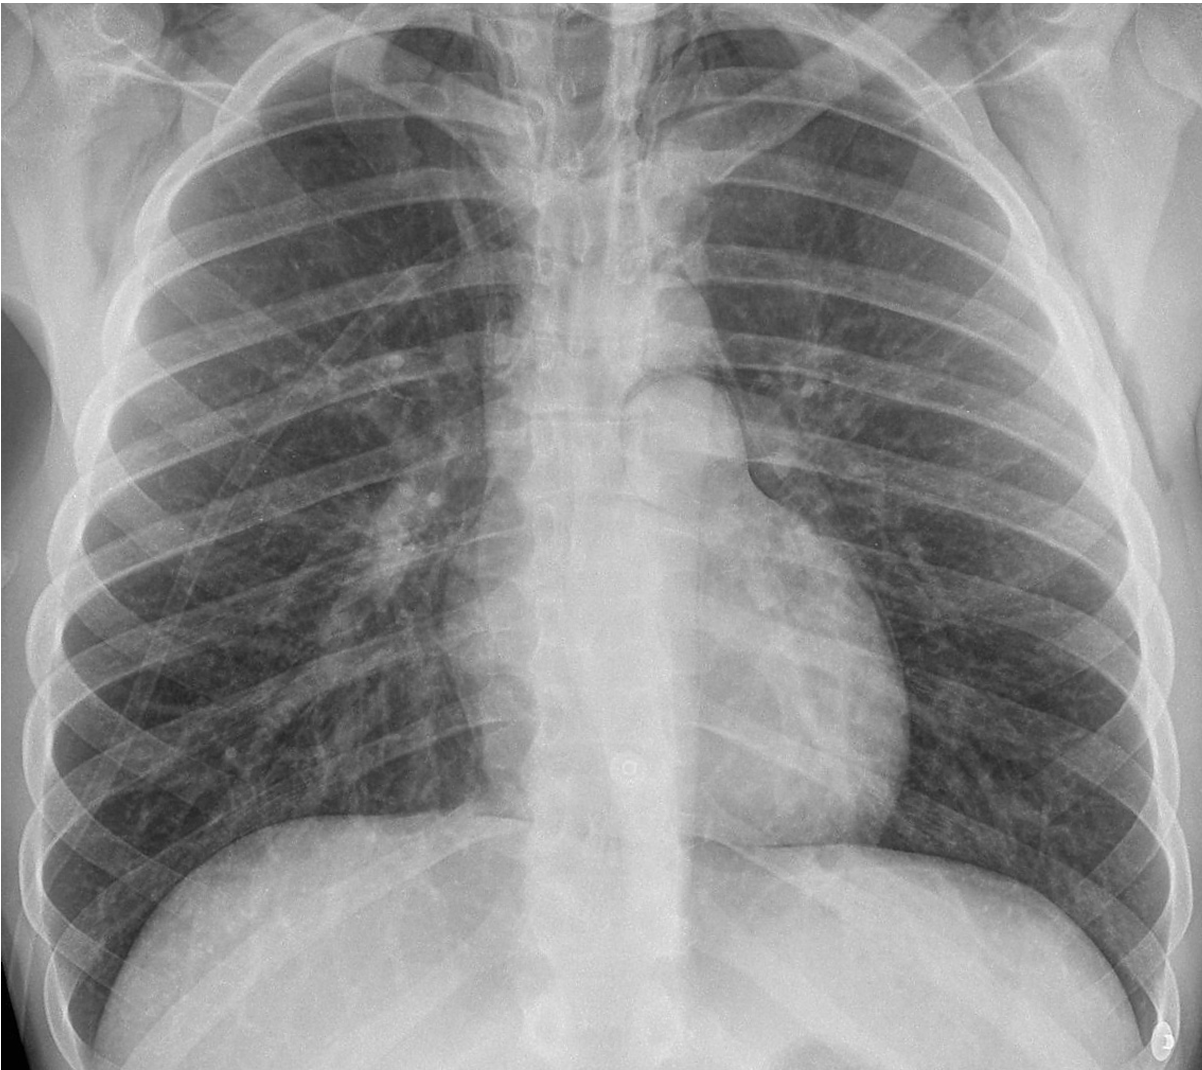

Question 9 (18 marks) 9 minutes

A 48 year old female presents to ED with shortness of breath. This xray is taken soon after arrival.

A CXR is taken- see props booklet- page 4.

a. State six (6) abnormal findings on this CXR. (6 marks)

The patient has a temperature of 39°C.

b. List five (5) factors that would determine your antibiotic choice. (6 marks)